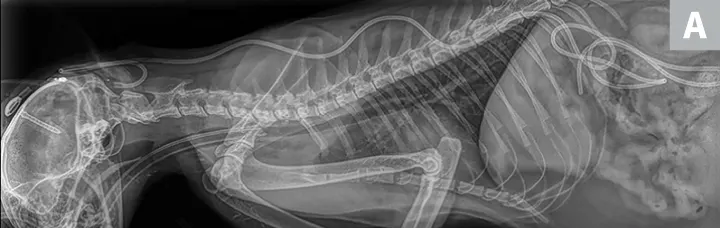

X-ray and CT images of a cat showing radiopaque ventriculoperitoneal shunt in place within skull.

FIGURE 5

(A) Postoperative lateral radiograph and (B) transverse CT image showing a ventriculoperitoneal shunt placed in a cat. Although the well was not flush with the skull, the shunt appeared stable after the sutures were tightened. The cat did well after surgery. Images courtesy of Dr. Eric Glass, Red Bank Veterinary Hospital/Compassion First Pet Hospitals

Surgical placement of a shunt is preferred, especially when medical management fails.1,2,11,12 Because return to normal condition is uncommon following surgery, the goal of shunt placement is improvement in clinical signs. Most commonly used is a ventriculoperitoneal shunt (Figure 5), which diverts CSF from the ventricular system through a tube tunneled through the subcutaneous tissues to the abdomen, where CSF is then reabsorbed.1,2 Patients with mild-to-moderate hydrocephalus often do well postoperatively; patients with severe hydrocephalus and only a thin rim of brain parenchyma are at higher risk for postoperative complications.1,2,9 If too much CSF is removed (ie, overshunting), the brain parenchyma may collapse, resulting in tearing of meningeal vessels and hemorrhage.1,2 Other postoperative complications can include undershunting; shunt infection or obstruction, which may necessitate replacement; and/or seizures.1,2